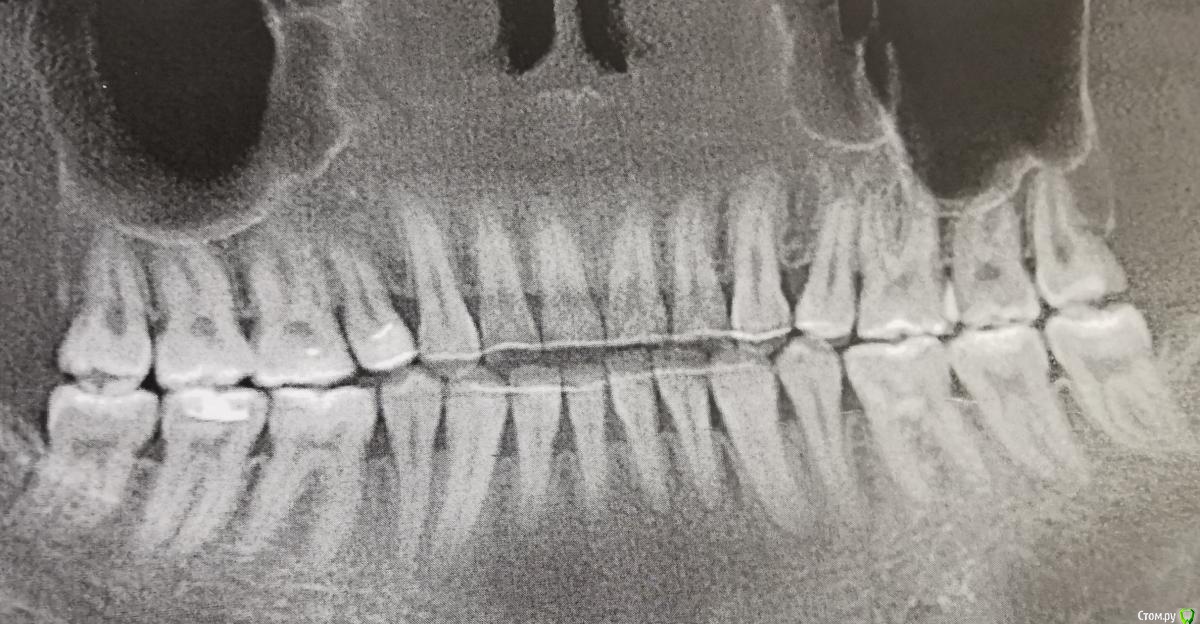

Даша45_ Опубликовано 15 июня, 2020 Поделиться Опубликовано 15 июня, 2020 Здравствуйте. Мне 29лет.Не помню когда точно начались проблемы, но в 2012 когда мне было 21 год Десна уже начала убывать. Тогда жила в маленьком городе. Ставили просто уколы и витамины. Десна уходила снизу, ничего не шаталось. Не было воспаление, крови при чистки, боли. Ничего. В 2016 году в начале года когда мне было 24 года я одела брекеты по настоянию врачей. Говорили при неправильном прикусе и скученности зубов Десна будет больше уходить. Сняла брекеты через 1.5 года. Все хорошо поставили. Сейчас ровно 3 года как сняла брекеты. Снизу Десна на передних зубах ушла больше. Иногда бывают неприятные чувства. Но ничего не воспалена и крови нет. Делала в этом году томографию и врачи сравнили с 2018 годом говорят изменений по кости нет. Все стабильно. Прикрепляю последнюю томографию. Что меня ждёт в будущем? Все очень плохо? Смогут ли поставить имплант или коронки с такой костью? Сьемную челюсть конечно в таком возрасте бы не хотелось Ссылка на комментарий

Даша45_ Опубликовано 15 июня, 2020 Автор Поделиться Опубликовано 15 июня, 2020 ПРФ - терапия иногда помогает.В перспективе возможно шинирование боковых зубов по жевательным поверхностям.С эндокринологией все в порядке?Да, гормоны сдавала, узи гортани, зова нет. Всё в порядке. У меня уже стоят ретейнеры они почти как шинирование. ПРФ пока не надо говорят если беременность планирую. А на этом снимке кость хорошо видна или надо было грузить файл с диска томография? Если зубы выпадут мне смогут поставить имплпниы или коронки с такой костью? Съемную челюсть не хочу Ссылка на комментарий

Даша45_ Опубликовано 17 июня, 2020 Автор Поделиться Опубликовано 17 июня, 2020 Уже писала недавно. Проблемы с десной с 2011-2012гг.В период с 2015-2017 носила брекеты по настоянию врачей. Сняла ровно 3 года назад. Делала кт говорят страшно ушла кость и за ней и Десна. Сравнивали кт 2018 года и этого сказали изменений нет. Воспаление, гноя, кровоточивости нет. Ну спереди очень ушло за 3 года. Иногда неприятные ощущения. Что делать? Планирую беременностт. Насколько все плохо. Мне 29лет Ссылка на комментарий